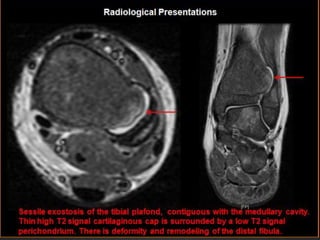

MRI

• MR imaging is the best radiologic imaging method

evaluating hyaline cartilage cap.

• The high water content in non mineralized areas of the

cartilage cap has intermediate to low signal intensity on

T1-weighted images and high signal intensity on T2-

weighted images.

• Mineralized areas in the cartilage cap had low signal

intensity on T1 and T2-weighted images

• In young patients with active growth and maturation from

normal enchondral ossification in the cartilage cap may be

marked heterogeneity both T1-weighted images and T2-

weighted images because of the mixture of non

mineralized and mineralize cartilage tissues.

Selected T1 and T2 weighted images shown above demonstrate a

broad based exophytic lesion of bone. The marrow space of the

bone and the lesion are contiguous. There are areas of T2

brightening at the periphery of the lesion, but without frank invasion

of the surrounding tissues.